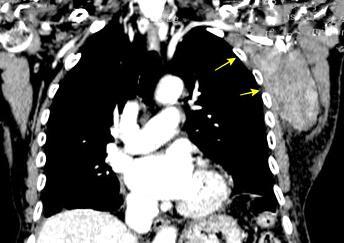

Linfoma NH de cél. B. Invasión Transtorácica.

Afectación axilar